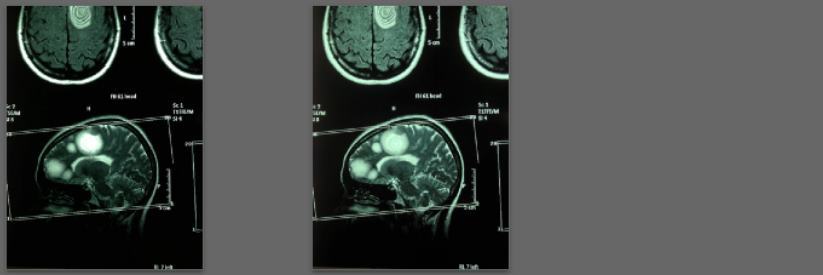

Before/after MRI images for one of 1,000+ patients of Dr. Coimbra

2008 Convulsive seizures Diagnosis: Balo’s concentric hemiparesis

Starting daily dose 25,000 IU; increased in stages to 80,000 IU on October 28, 2010. Asymptomatic since 2010.

2008 MRI

2013 MRI